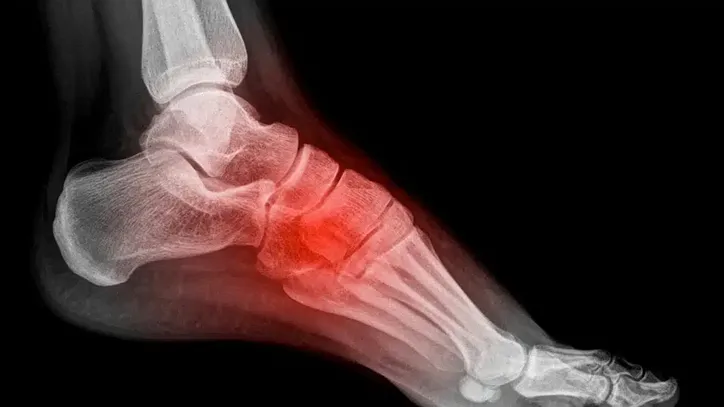

Segundo ele, o pé é dividido em três regiões: retropé, mediopé e antepé, de modo que a Lisfranc é uma articulação localizada entre o mediopé e o antepé.

“Essa articulação é extremamente importante porque toda força que a gente faz pra andar, para correr e para qualquer atividade que retenha a carga sobre o pé passa pela Lisfranc. Se você tiver alguma lesão nessa articulação e ela não cicatrizar de maneira adequada ou não for tratada de maneira adequada, ela traz uma limitação muito grande para os pés.”, iniciou Moreno.

Ainda segundo ele, o comprometimento do Lisfranc pode acontecer de três formas:

- fratura na região dos ossos da articulação de Lisfranc;

- lesão isolada do ligamento de Lisfranc;

- uma lesão complexa que envolve tanto fraturas dos ossos da articulação de Lisfranc, quanto a lesão do ligamento.

Marcus Moreno analisa que a lesão de Camutanga foi uma lesão complexa, o mais grave dos três cenários.